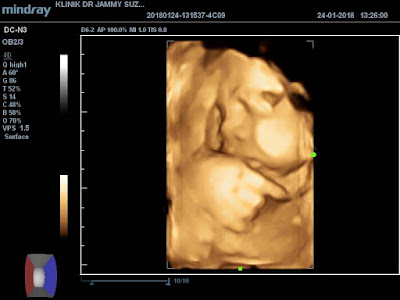

24 JANUARY 2018 (31 Weeks 5 Days)

Klinik Dr Jammy Suzana , Taman Ilmu Nibong Tebal

Untuk scan 3D/4D ni kena buat appointment , tak macam scan 2D hari tu just daftar dan terus scan . Aku buat appointment 18 January 2018 dan dia bagi date suruh datang balik pada 24 January 2018 12.30pm . Kali ni untuk 3D/4D scan Rm 100.00 , dapat CD (softcopy gambar + video ) + gambar (print) + detail baby .

Kali ni pon abah yang hantar jugak , tapi mak teman dalam klinik cuma nak masok bilik Dr ja mak tak masok . Dan macam biasa la Dr akan check saiz baby + berat baby + kedudukan baby + kedudukan uri + check air ketuban + fizikal baby . Kali ni aku tak tanya dah jantina nampak ka tak , tapi doktor tu yang tanya aku .

Dr pon check la bahagian kemaluan dia , tanpa disangkal lagi . Memang baby boboy , nampak jelas sangat (anak ibu tak dak malu-malu dah) . Dalam hati bersyukur sangat-sangat , Alhamdulillah .

Sex : xy

Lepas tu baru Dr start 3D/4D scan , tengok muka baby . Terharu sangat bila dapat tengok tu walaupun lindung tangan dia sikit-sikit , mula-mula tak perasan apa dia buat . Lama-lama perati rupanya anak ibu isap ibu jari . Alalalaa omeynyee dia . Dr amek masa lama sangat nak dapat muka jelas , sebab baby aktif sangat dok begerak kat dalam perut . huhu

31 Weeks berat baby +- 1.8 kg (Dr kata tak besar sangat , tak kecil sangat)